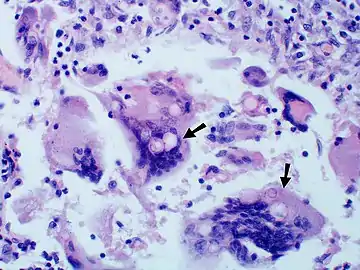

Large yeast-like fungi seen within giant cells at arrows. Large yeast-like fungi seen within giant cells at arrows. Budding yeasts in cytoplasm of giant cells at arrows. Broad-based budding and double contoured cell wall seen in the giant cell in the center is characteristic of Blastomyces dermatitidis.

Large yeast-like fungi seen within giant cells at arrows. Budding yeasts in cytoplasm of giant cells at arrows. Broad-based budding and double contoured cell wall seen in the giant cell in the center is characteristic of Blastomyces dermatitidis. Nodular skin lesions of blastomycosis, one of which is a bullous lesion on top of a nodule.